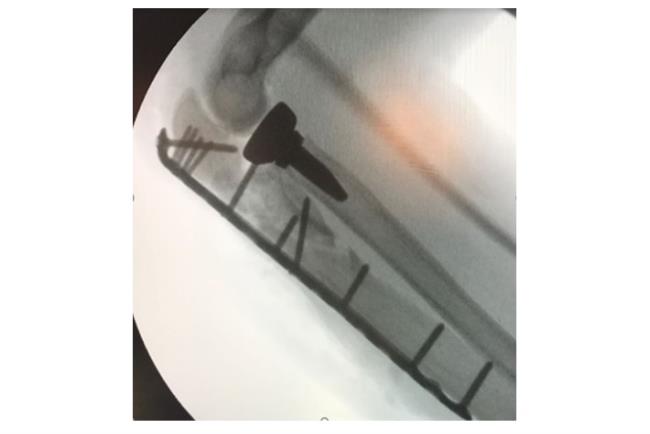

קיבוע שבר בעצם הטיביה | באדיבות פרופ' דורון נורמן

בשלב הראשון יתבצע צילום רנטגן. אם עולה חשד לכך שהשבר מערב גם את המפרק תתבצע גם בדיקת CT לשם הדמיה תלת ממדית של האזור הפגוע וחלקי השבר אותם יש להרכיב כדי להשיב למפרק את תנועתו התקינה. לרוב, כדי לטפל בשברים מורכבים יתבצע ניתוח ולא קיבוע בגבס.מטרת הטיפול בגבס היא קיבוע המצב הקיים ועל כן במקרה של שבר מורכב טיפול זה לא יועיל בהשבת התפקוד המפרקי. לכן, כדי להשיב את המצב לקדמותו יש צורך בפתיחת המפרק, העמדת כל אחד מחלקי העצם במקומו וחיבור החלקים אחד אל השני. הניתוח והקיבוע נעשים ע"י פלטות ברגים ומסמרים תוך לשדיים העשויים טיטניום או סוג של פלדת אל חלד.